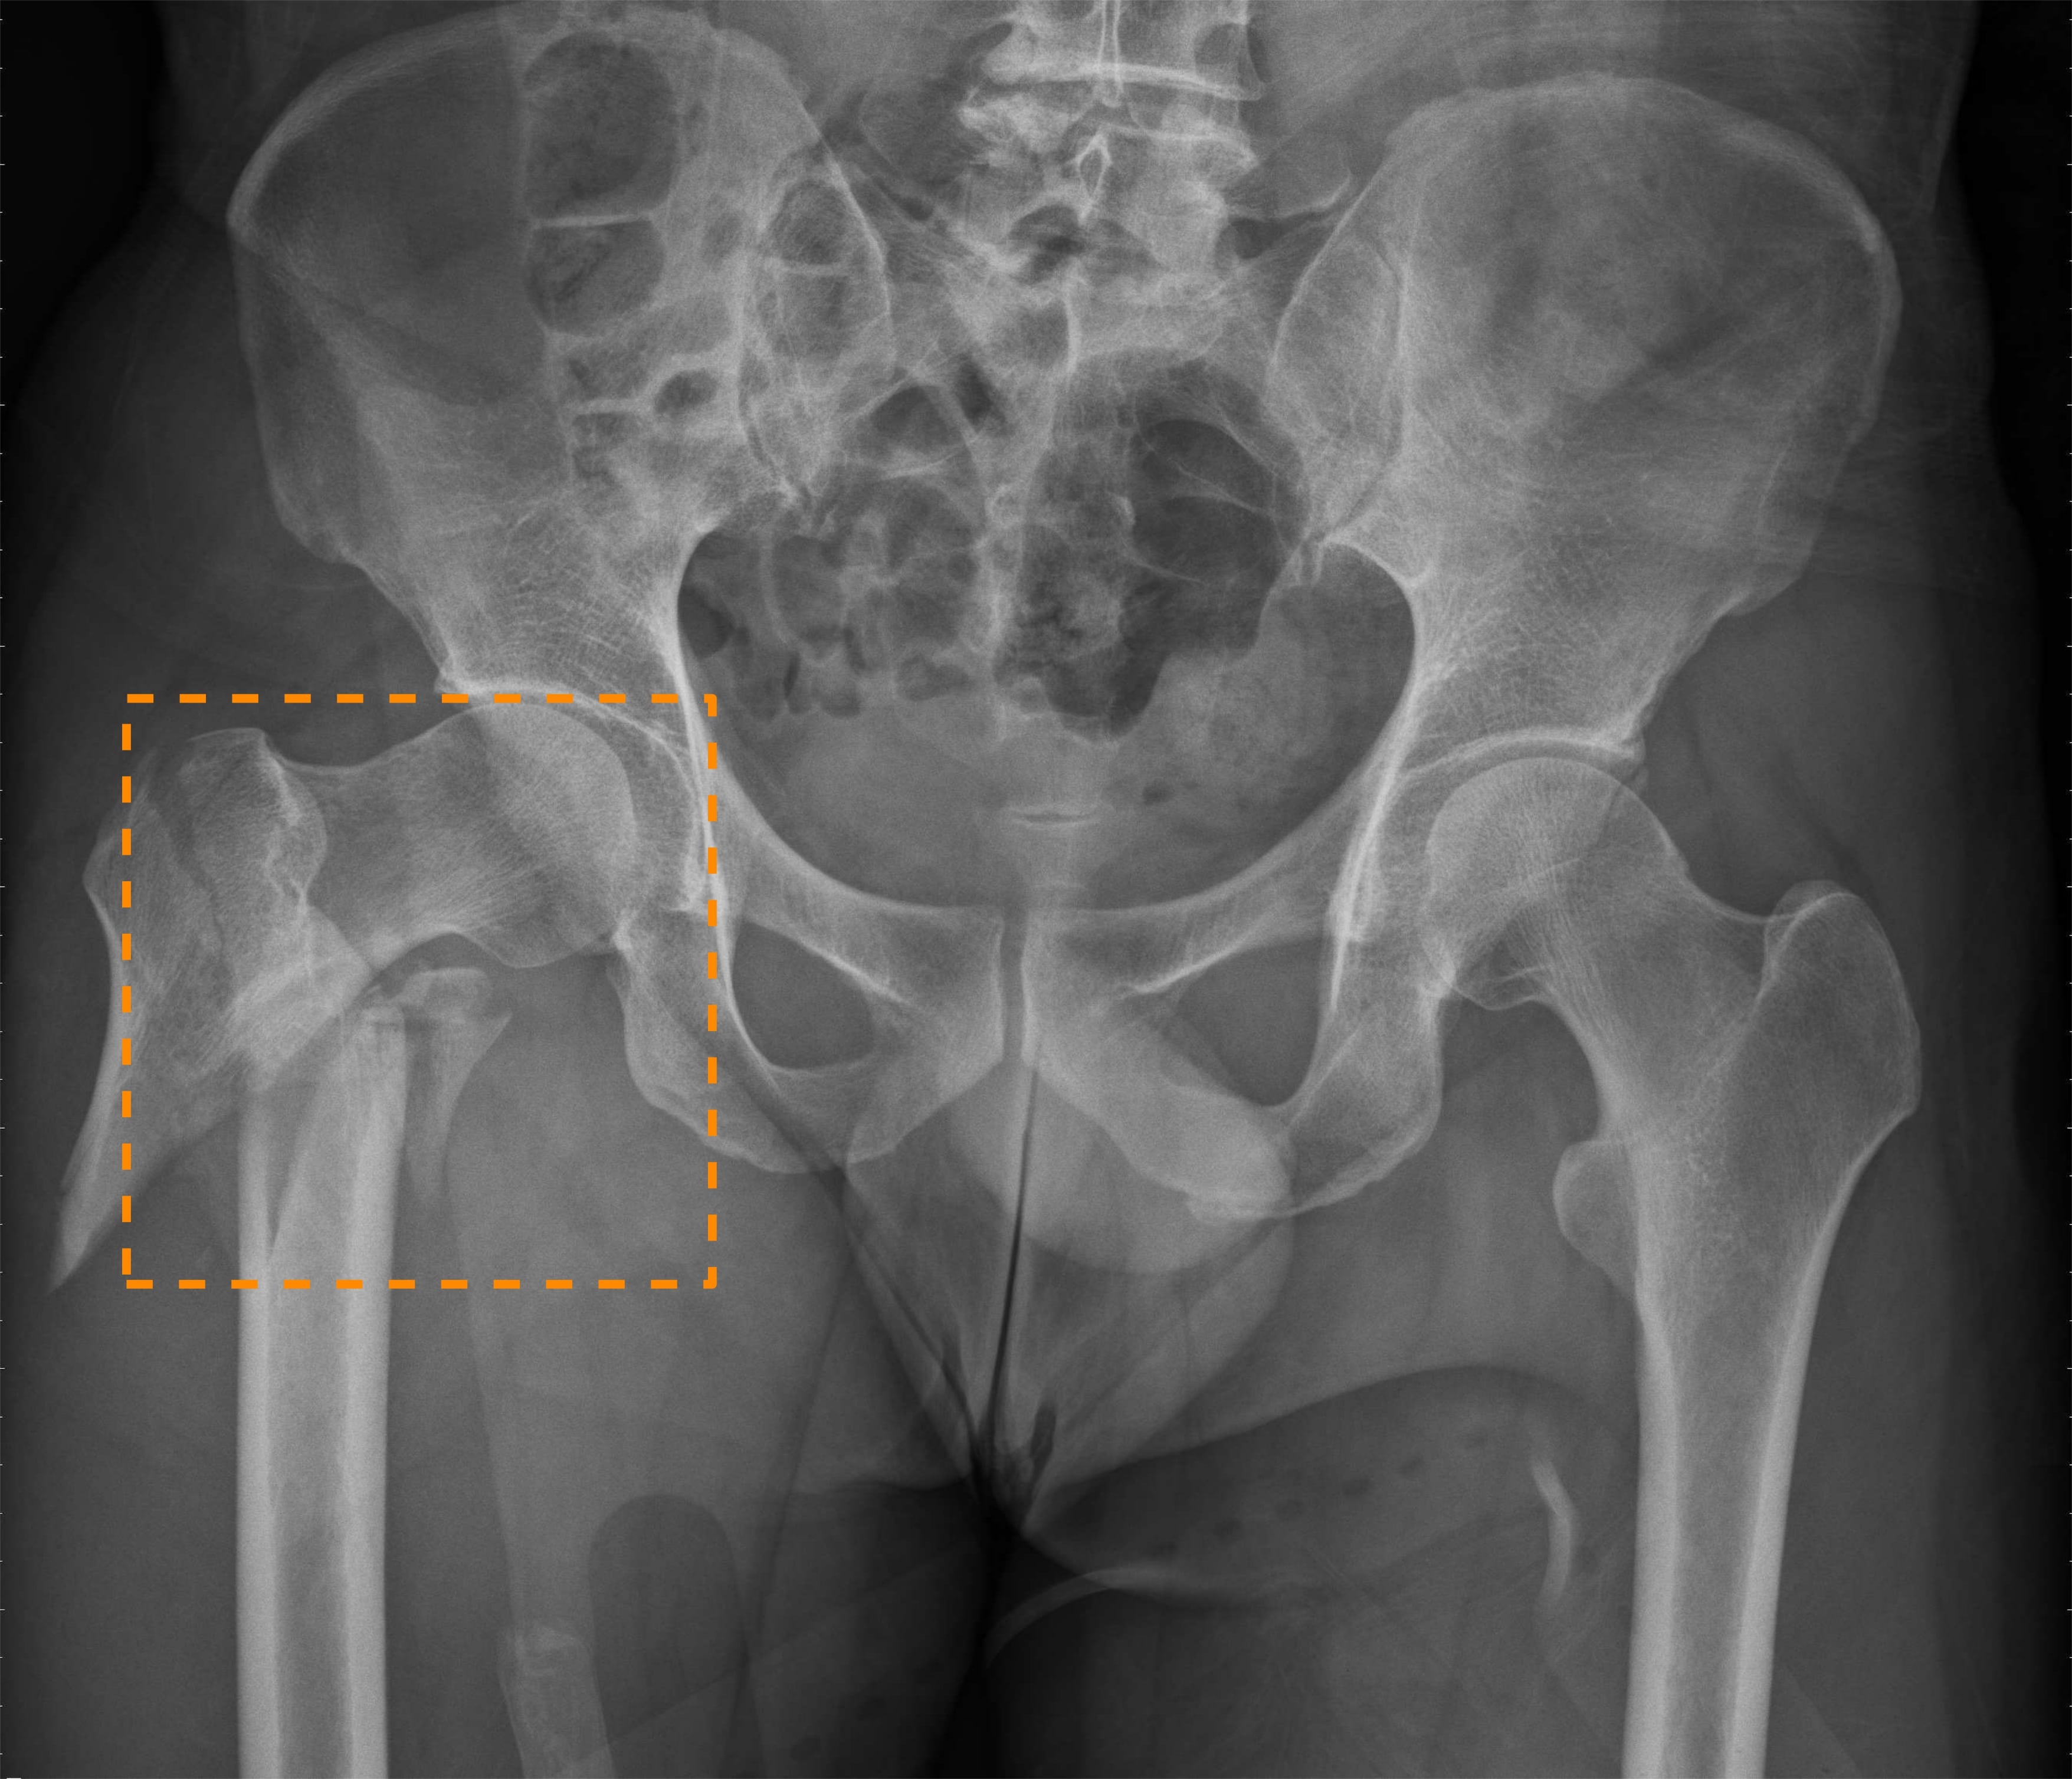

Refer to caption

Figure 1: Example \acPXR images of hip and pelvic fractures. (Left) Hip fracture. (Middle) Superior and inferior pubic ramus fracture. (Right) Iliac wing fracture.

Nonetheless, the above prior work all only focuses on diagnosing hip fractures and does not attempt to classify the more complex pelvic fractures (fractures in three pelvic bones: the ilium, ischium, and pubis). As Fig. 1 illustrates, the makeup of pelvis fractures is much more complex, as there are a large variety of possible types with very different visual patterns at various locations. In addition, pelvic bones overlap with the lower abdomen, further confounding image patterns. Finally, unlike hip fractures, which occur at the femoral neck/head, pelvic fractures can occur anywhere on the large pelvis, both increasing the aforementioned image pattern combinatorial complexity and precluding automatic \acROI extraction based on anatomy alone, such as was done in prior work [4]. Thus, while using \acROI-based classification is even more desirable for pelvic fractures, it is paradoxically more challenging to extract said \acpROI.